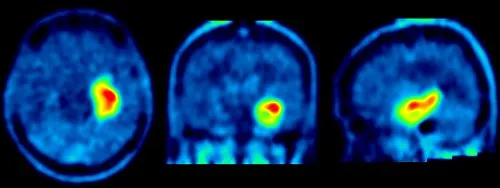

Wie die Durchblutung des Gehirns sichtbar gemacht wird (z. B. bei Demenz)

In der Neurologie ist SPECT ein wichtiges Werkzeug zur Beurteilung der Gehirndurchblutung. Mit speziellen Tracern können wir Bereiche im Gehirn identifizieren, die möglicherweise unterversorgt sind. Dies ist entscheidend für die Diagnose und Verlaufsbeurteilung von Erkrankungen wie Demenz (z. B. Alzheimer-Krankheit), Schlaganfällen oder Parkinson. Abnormale Durchblutungsmuster können uns Hinweise auf die zugrundeliegende neurologische Störung geben.